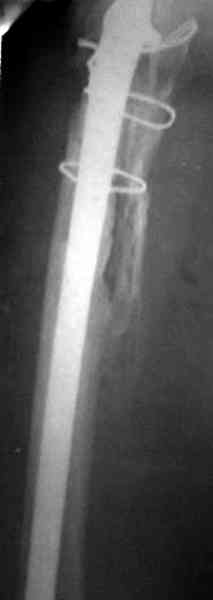

контрольный снимок сделали только на 21день после операции (№1) и с интервалом 5 дней второй снимок (№2)

Судя по всему, произошел раскол наружной стенки бедра и ножка находится вне костного канала. В таком случае

решение одно - удаление ножки и установка новой в расчете на дистальную фиксацию. Конктреную модель подсказать тяжело из-за низкого качества Р-грамм.

№3-6 снимки с осложнением